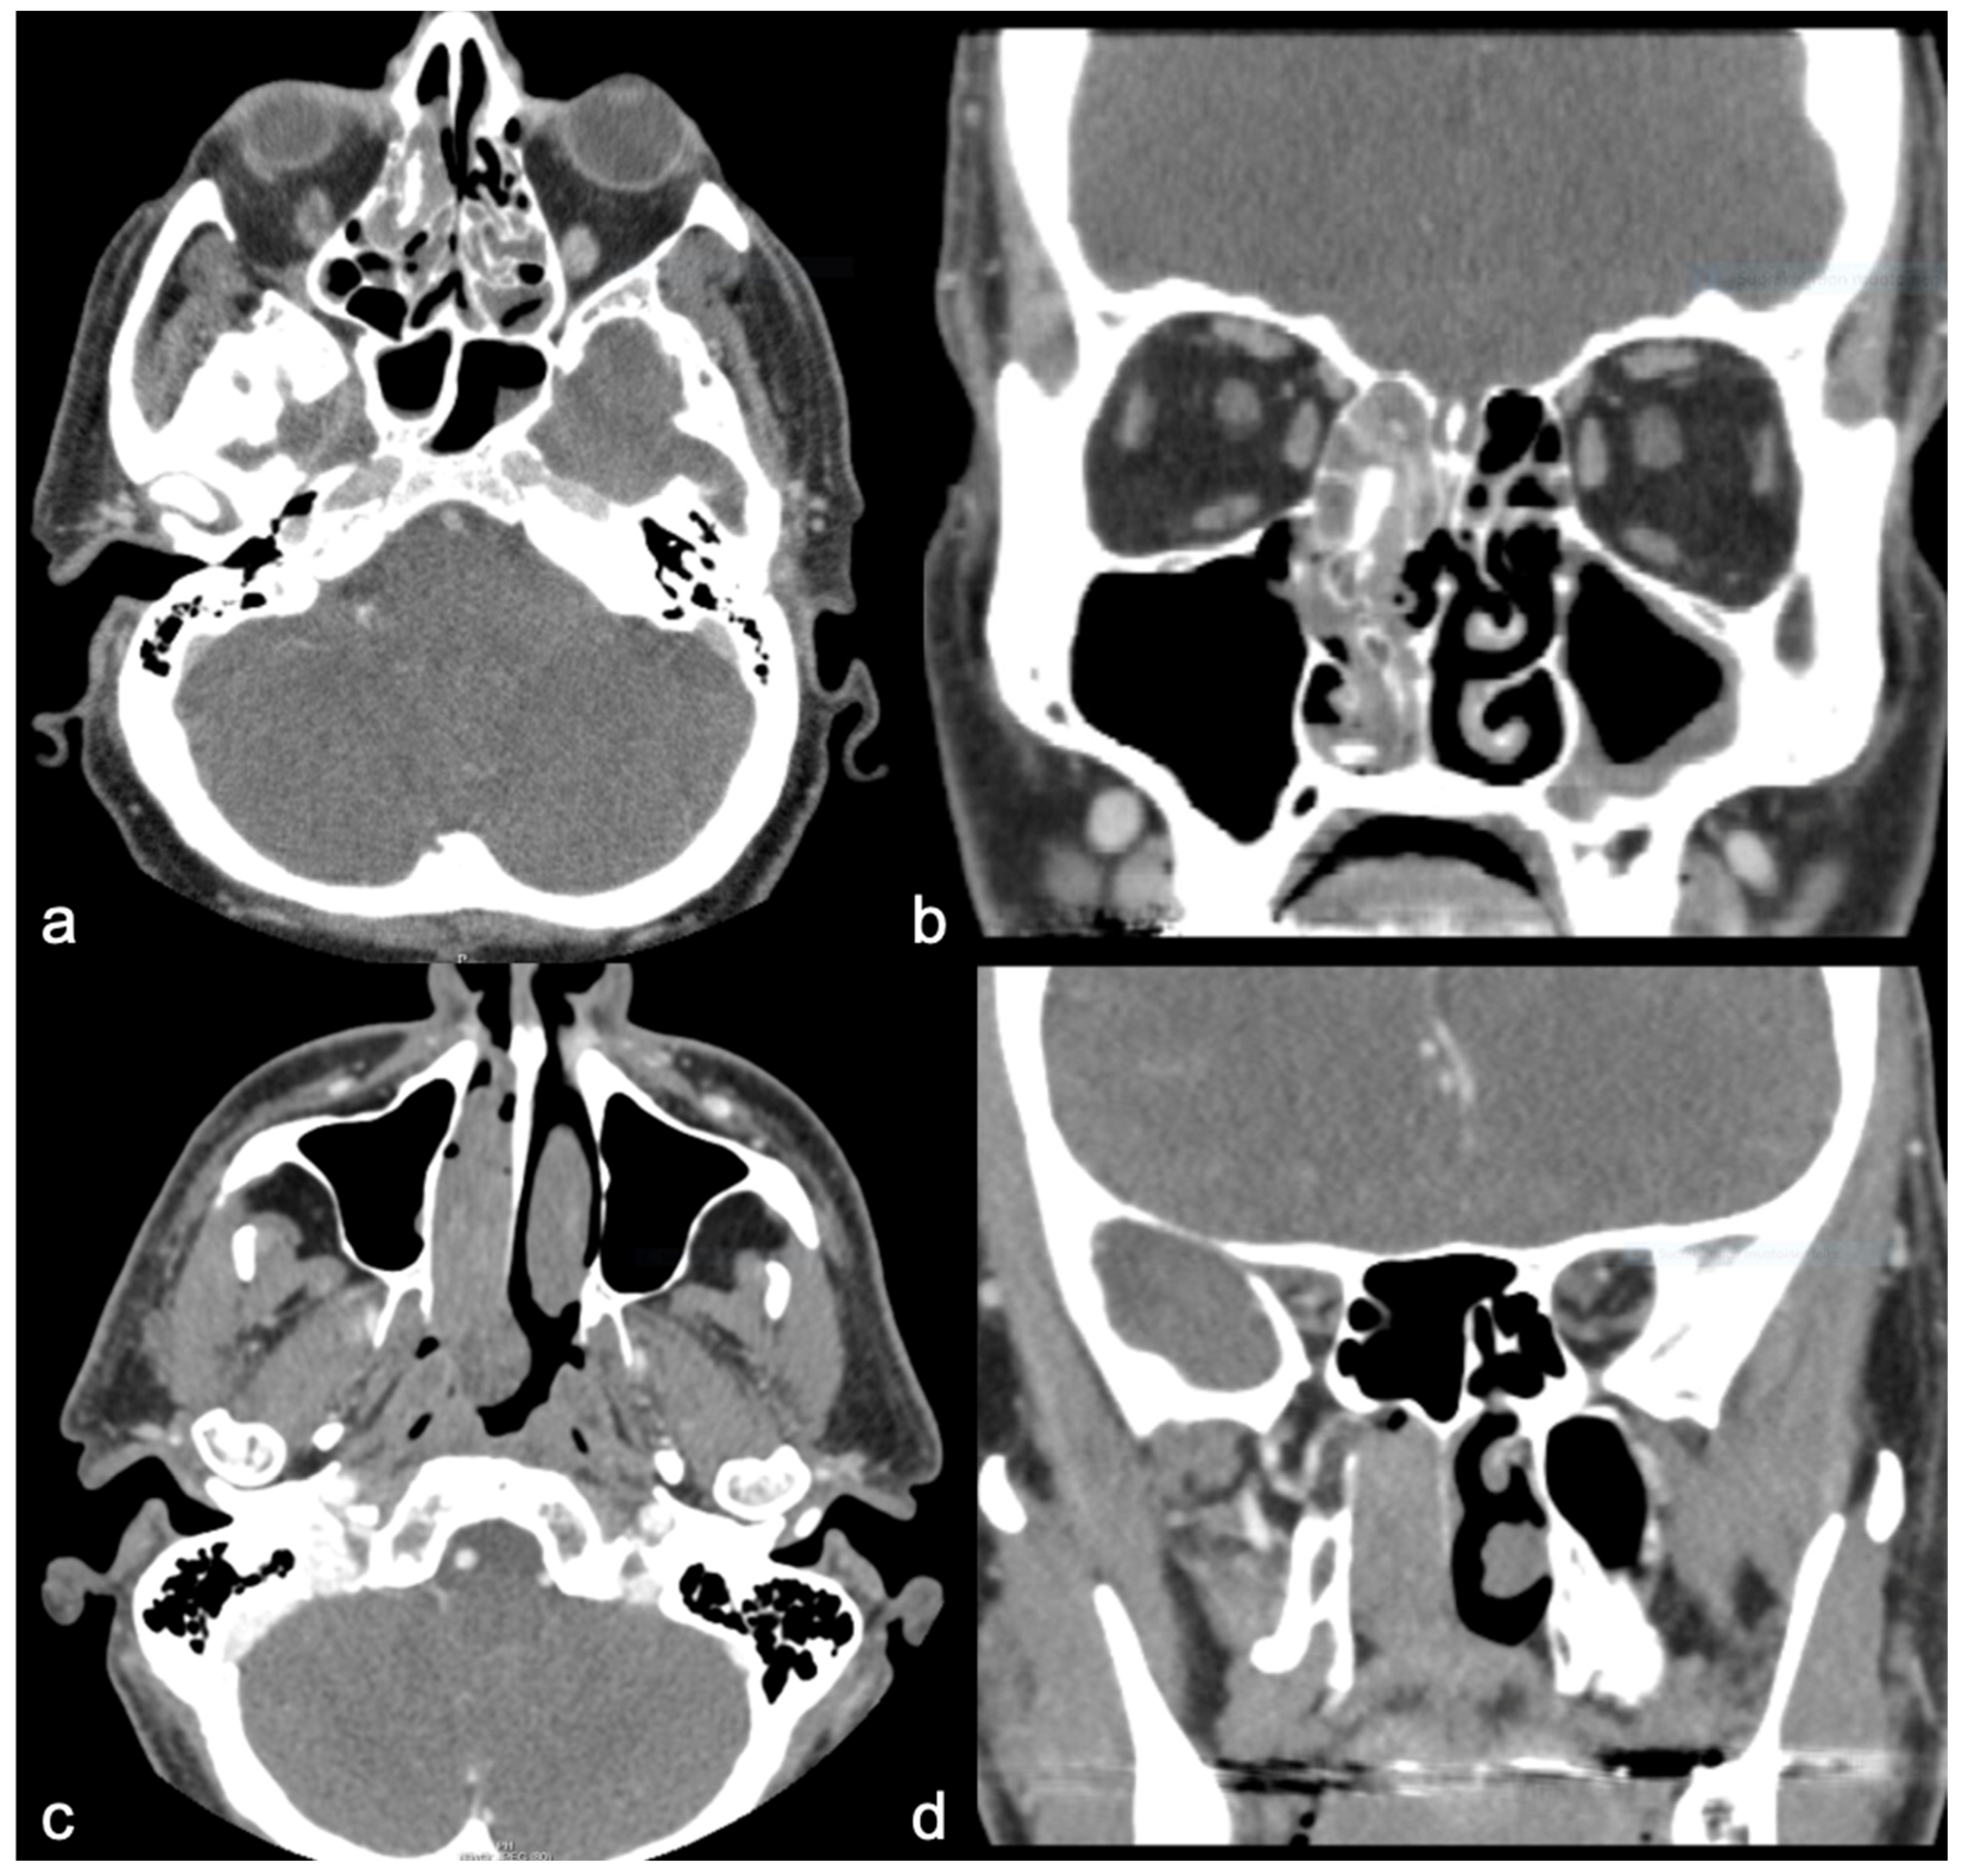

| Findings Only Found in SNIP-SCC | SNIP-SCC n (8) | SNIP n (8) |

|---|---|---|

| Orbit invasion | 12.5% (1) | 0% |

| Intracranial invasion | 25% (2) | 0% |

| Bone defect | ||

| Nasal cavity wall | 50% (4) | 0% |

| Maxillary | 50% (4) | 0% |

| Ethmoid | 25% (2) | 0% |

| Sphenoid | 12.5% (1) | 0% |

| Frontal | 25% (2) | 0% |

| Some differences between groups | SNIP-SCC n (8) | SNIP n (8) |

| Shape of tumor | ||

| Polypoid | 50% (4) | 75% (6) |

| Unsharp | 50% (4) | 25% (2) |

| Tumor location | ||

| Unilateral | 50% (4) | 87.5% (7) |

| Bilateral | 50% (4) | 12.5% (1) |

| Nasal cavity wall | 100% (8) | 100% (8) |

| Maxillary | 50% (4) | 62.5% (5) |

| Ethmoid | 87.5% (7) | 75% (6) |

| Sphenoid | 25% (2) | 0% |

| Frontal | 25% (2) | 37.5% (3) |

| CT enhancement * | 87.5% (7/8) | 62.5% (5/8) * |

| Site of hyperostosis on CT | ||

| Nasal cavity wall | 0% | 25% (2) |

| Maxillary | 12.5% (1) | 0% |

| Ethmoid | 0% | 25% (2) |

| Sphenoid | 0% | 0% |

| Frontal | 12.5% (1) | 0% |

| No differences between groups | SNIP-SCC n (8) | SNIP n (8) |

| Mean diameter of tumor, mm (range) | 57 (30–87) | 48 (20–70) |

| Surface of the tumor | ||

| Smooth | 25% (2) | 12.5% (1) |

| Rough | 75% (6) | 75% (6) |

| Tumor calcification | 25% (2) | 25% (2) |